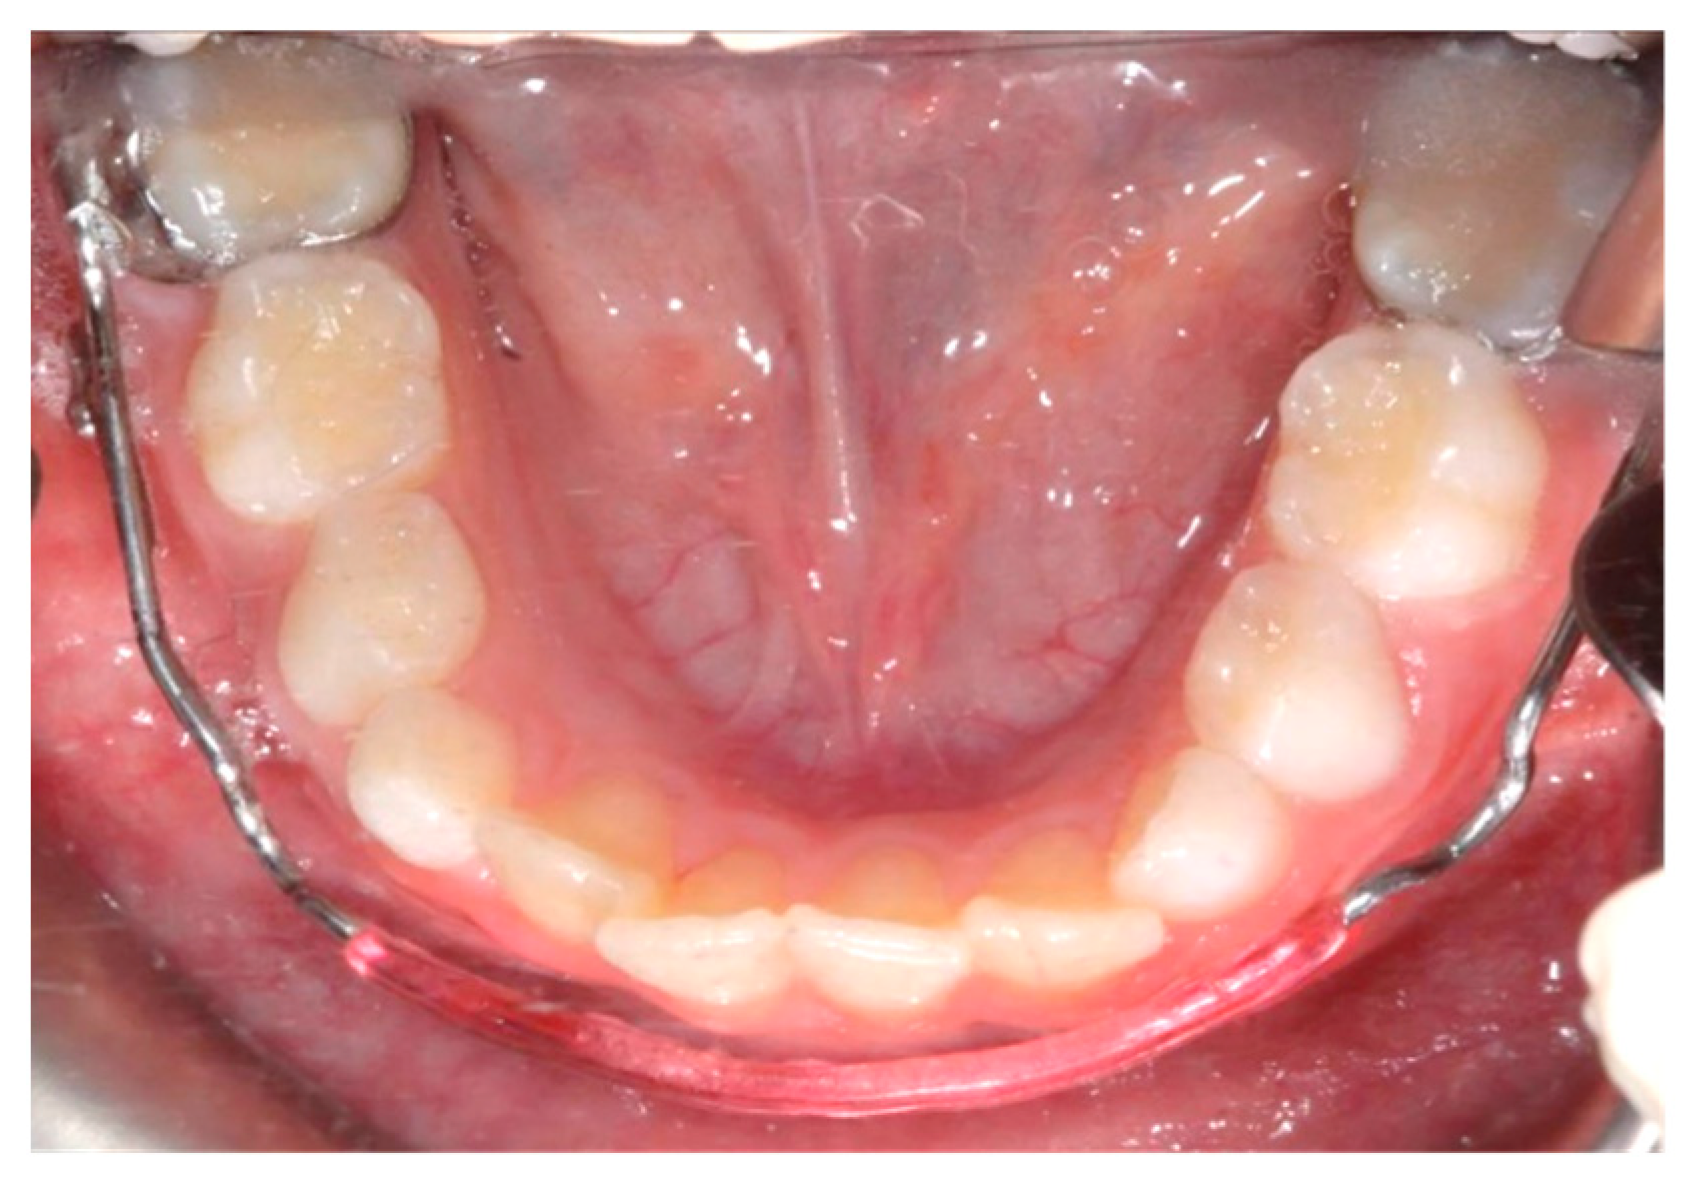

The lower jaw is considered the guiding arch in crowding therapy because it is difficult to modify its perimeter due to the more compact bone structure and the continuity with the mandibular branch, which does not allow for distalization [37,41]. In addition, the symphysis cartilage ossifies in the first year of life, so it is not possible to perform an orthopedic bone expansion, as in the upper jaw, working at the level of the median palatine suture [41,42]. The modalities of space recovery in mixed dentition are: arch perimeter increment, reduction in mesiodistal widths of teeth and serial extractions [2,43,44]. In the upper arch, the expansions are quite stable, but inferiorly, it is universally recognized that the expansion of the intercanine diameter always recurs, whereas expansion at the molar level is quite stable, which should be considered [27,45,46,47]. The space that can be recovered in the lower arch depends on the type of sector: in general, in the posterior sector, utilizing a lip bumper-style device, it is possible to recover a maximum of 2 mm of space per molar distalization in the posterior regions. At the molar level in the lateral sectors, the arch length could increase by about 0.4 mm; at the canine level, the arch length increases about 0.7 mm [48]. The vestibularization of one millimeter of the incisal margin in the anterior sector results in the gain of one millimeter of arch space, or roughly a ratio of one to one (changing the arch form) [47]. Schwarz’s appliance (Figure 3) and lip bumper (Figure 4) are two commonly used appliances for increasing lower dental arch dimensions [49]. In their study, Vincenzo Quinzi et al. compared the effects of these appliances on reducing mandibular crowding by increasing lower arch dimensions [27]. The study included twenty subjects (10 males and 10 females). Ten patients were treated with Schwarz’s appliance, and ten with lip bumper. The Schwarz appliance was more effective in increasing intercanine arch dimensions and arch perimeter, although the lip bumper reached a greater increase in arch length [27]. Since the 1970s, there have been reports of spontaneous changes in mandibular dentition caused by maxillary expansion [31,50]. Di Ventura et al. assessed the consequences of rapid maxillary expansion (RME) anchored to primary molars on the mandibular arch. A total of 54 patients were recruited for this study and divided into two groups: a test group (21 patients, 7.4 ± 1.2 years) who underwent RME, and a control group (17 patients, 7.3 ± 1.1 years old) who did not receive any treatment. The results of this study showed a significant increase in interdental width in the lower arch after 9 months of RME therapy [31]. Olivia Griswold et al. evaluated the changes in sagittal mandibular incisors’ position in response to lip bumper therapy using CBCT [32]. In this study, the authors compared a group that was treated only with rapid maxillary expansion (experimental group) and an RME + LB (lip bumper) group (control group) [32]. The CBCTs were placed in 3D on the mandibular structure, and the angular and linear alterations in the mandibular incisors throughout LB therapy were assessed. In the investigation, there was no statistically significant difference in the degree of mandibular incisor protrusion between the two groups; the lip bumper did not generate substantial proclination, protrusion or extrusion of the mandibular incisors. [13]. Air-rotor stripping (ARS) (Figure 5) is a technique for creating space during the mixed dentition period by reducing interproximal enamel thickness. Yahya B. Nakhjavani et al. assessed the efficacy of the mesial stripping of mandibular deciduous canines for the correction of rotated and lingually erupted lateral incisors in 42 patients with <3 mm mandibular crowding [33]. In this study, the mesial stripping of mandibular primary canines resulted in full crowding correction; in just few cases, the amount of crowding did not reach zero, and a small crowding in the range of 0.06 to 0.1 mm remained [33]. The extraction of all the first premolars with subsequent orthodontic treatment is the most used method to relieve dental crowding [51]. The importance and timing of extraction as a component of orthodontic therapy for late incisor crowding have been well investigated [35]. No difference in late incisor crowding is shown by the data, regardless of whether serial extraction or early or late premolar extraction is performed prior to orthodontic treatment. Additionally, selecting a non-extraction orthodontic procedure has been linked to post-retention crowding [35]. Maurits Persson et al. investigated changes in the mandibular incisor area from early adolescence to late adulthood in patients with a class I crowding malocclusion treated in the mixed dentition by the extraction of all first premolars without subsequent orthodontic treatment [35]. The extraction group included 24 subjects who had all their first premolars extracted at a mean age of about 11.5 years to treat a class I space deficiency malocclusion. The control group included 21 subjects who had normal occlusions at the age of 13 years [35]. The extraction group showed no improvements in lower incisor irregularity, and a significant increase in lower tooth space insufficiency into adulthood. Lower incisor irregularity and space shortage developed significantly in the control group throughout late adulthood [35]. Premolar extraction is the sole treatment option for severe crowding in a class I occlusion, allowing for spontaneous adjustments and more stable incisor alignment in late adulthood, according to the authors [35] (Table 2).

Figure 3. Schwarz’s appliance.